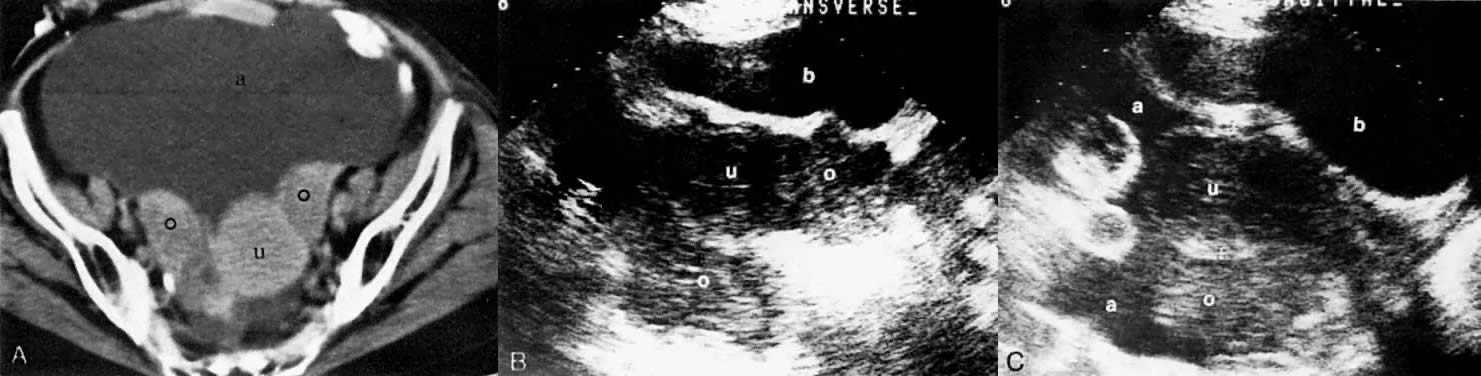

Ovarian adenocarcinoma involving both ovaries (o) and uterus (u) with ascites (a). CT scan of the pelvis (A) shows bilateral ovarian masses with ascites and uterine involvement on the left. Transverse (B) and sagittal (C) sonograms of the pelvis in a different patient show large, bilateral, irregular, and inhomogeneous ovarian masses inseparable from the uterus. Ascites is seen on the sagittal scan. The CT and ultrasound findings are consistent with at least stage II. (b, bladder.)